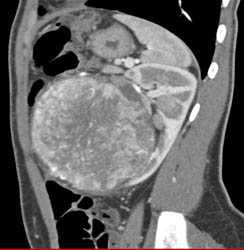

Sequence Shows Acute Pyelonephritis in the Left Kidney